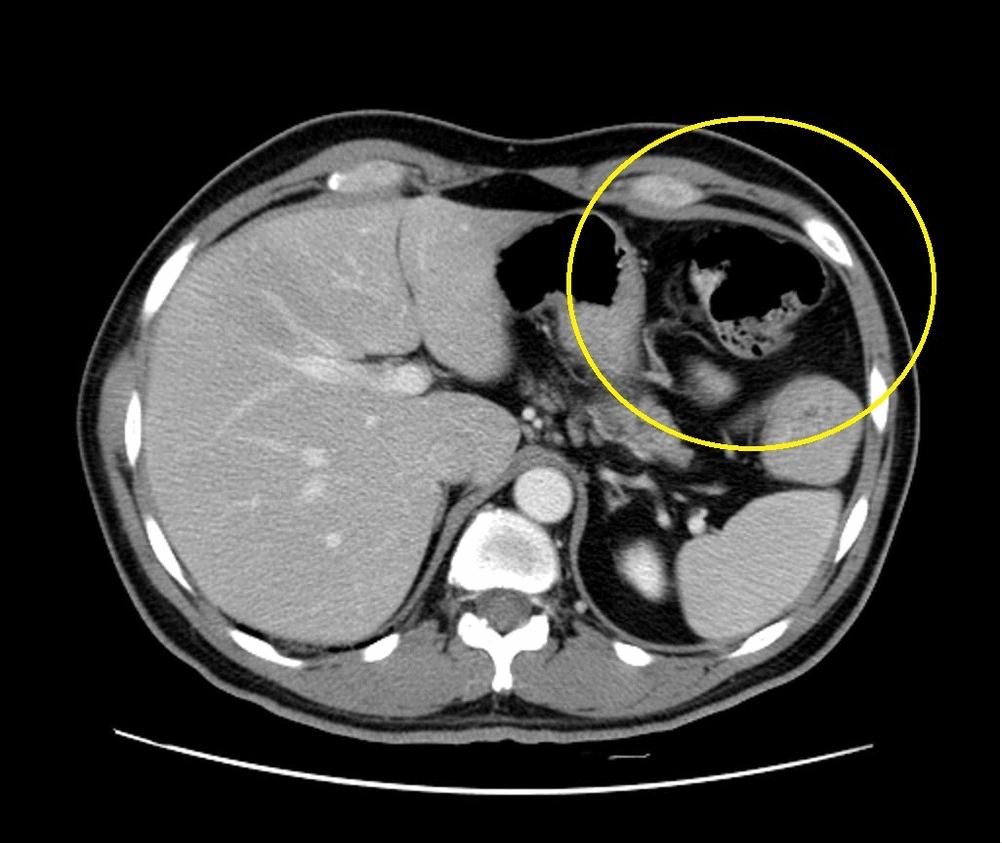

这其中最多的是视力障碍,约占后遗症的50%。这些都是因为刚地弓形虫导致的大脑水肿、钙化甚至脑积水引发的疾病。而这只是弓形虫在新生儿大脑中导致的病症,如果涉及全身,那么婴儿很可能死于发烧高热、心肌炎、黄疸、肝脾肿大等等并发症。